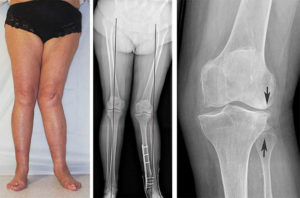

Относительно локализации, артроз может быть односторонним или двусторонним. Если патология поражает одно колено — скорее всего, причина заключается в травме. Фоновая патология вовлекает в процесс обе конечности. Однако, стоит заметить, что даже двусторонний артроз может протекать неравномерно. Иногда, с одной стороны наблюдается ранняя стадия болезни, а с другой — более тяжелая.

Каждая стадия имеет свои типичные рентгенологические признаки. Это важно для постановки диагноза и назначения лечения.

На снимке можно заметить сужение щели между суставными поверхностями, разрастание остеофитов и истощение костной ткани. В зависимости от стадии. варьируется степень выраженности данных признаков.